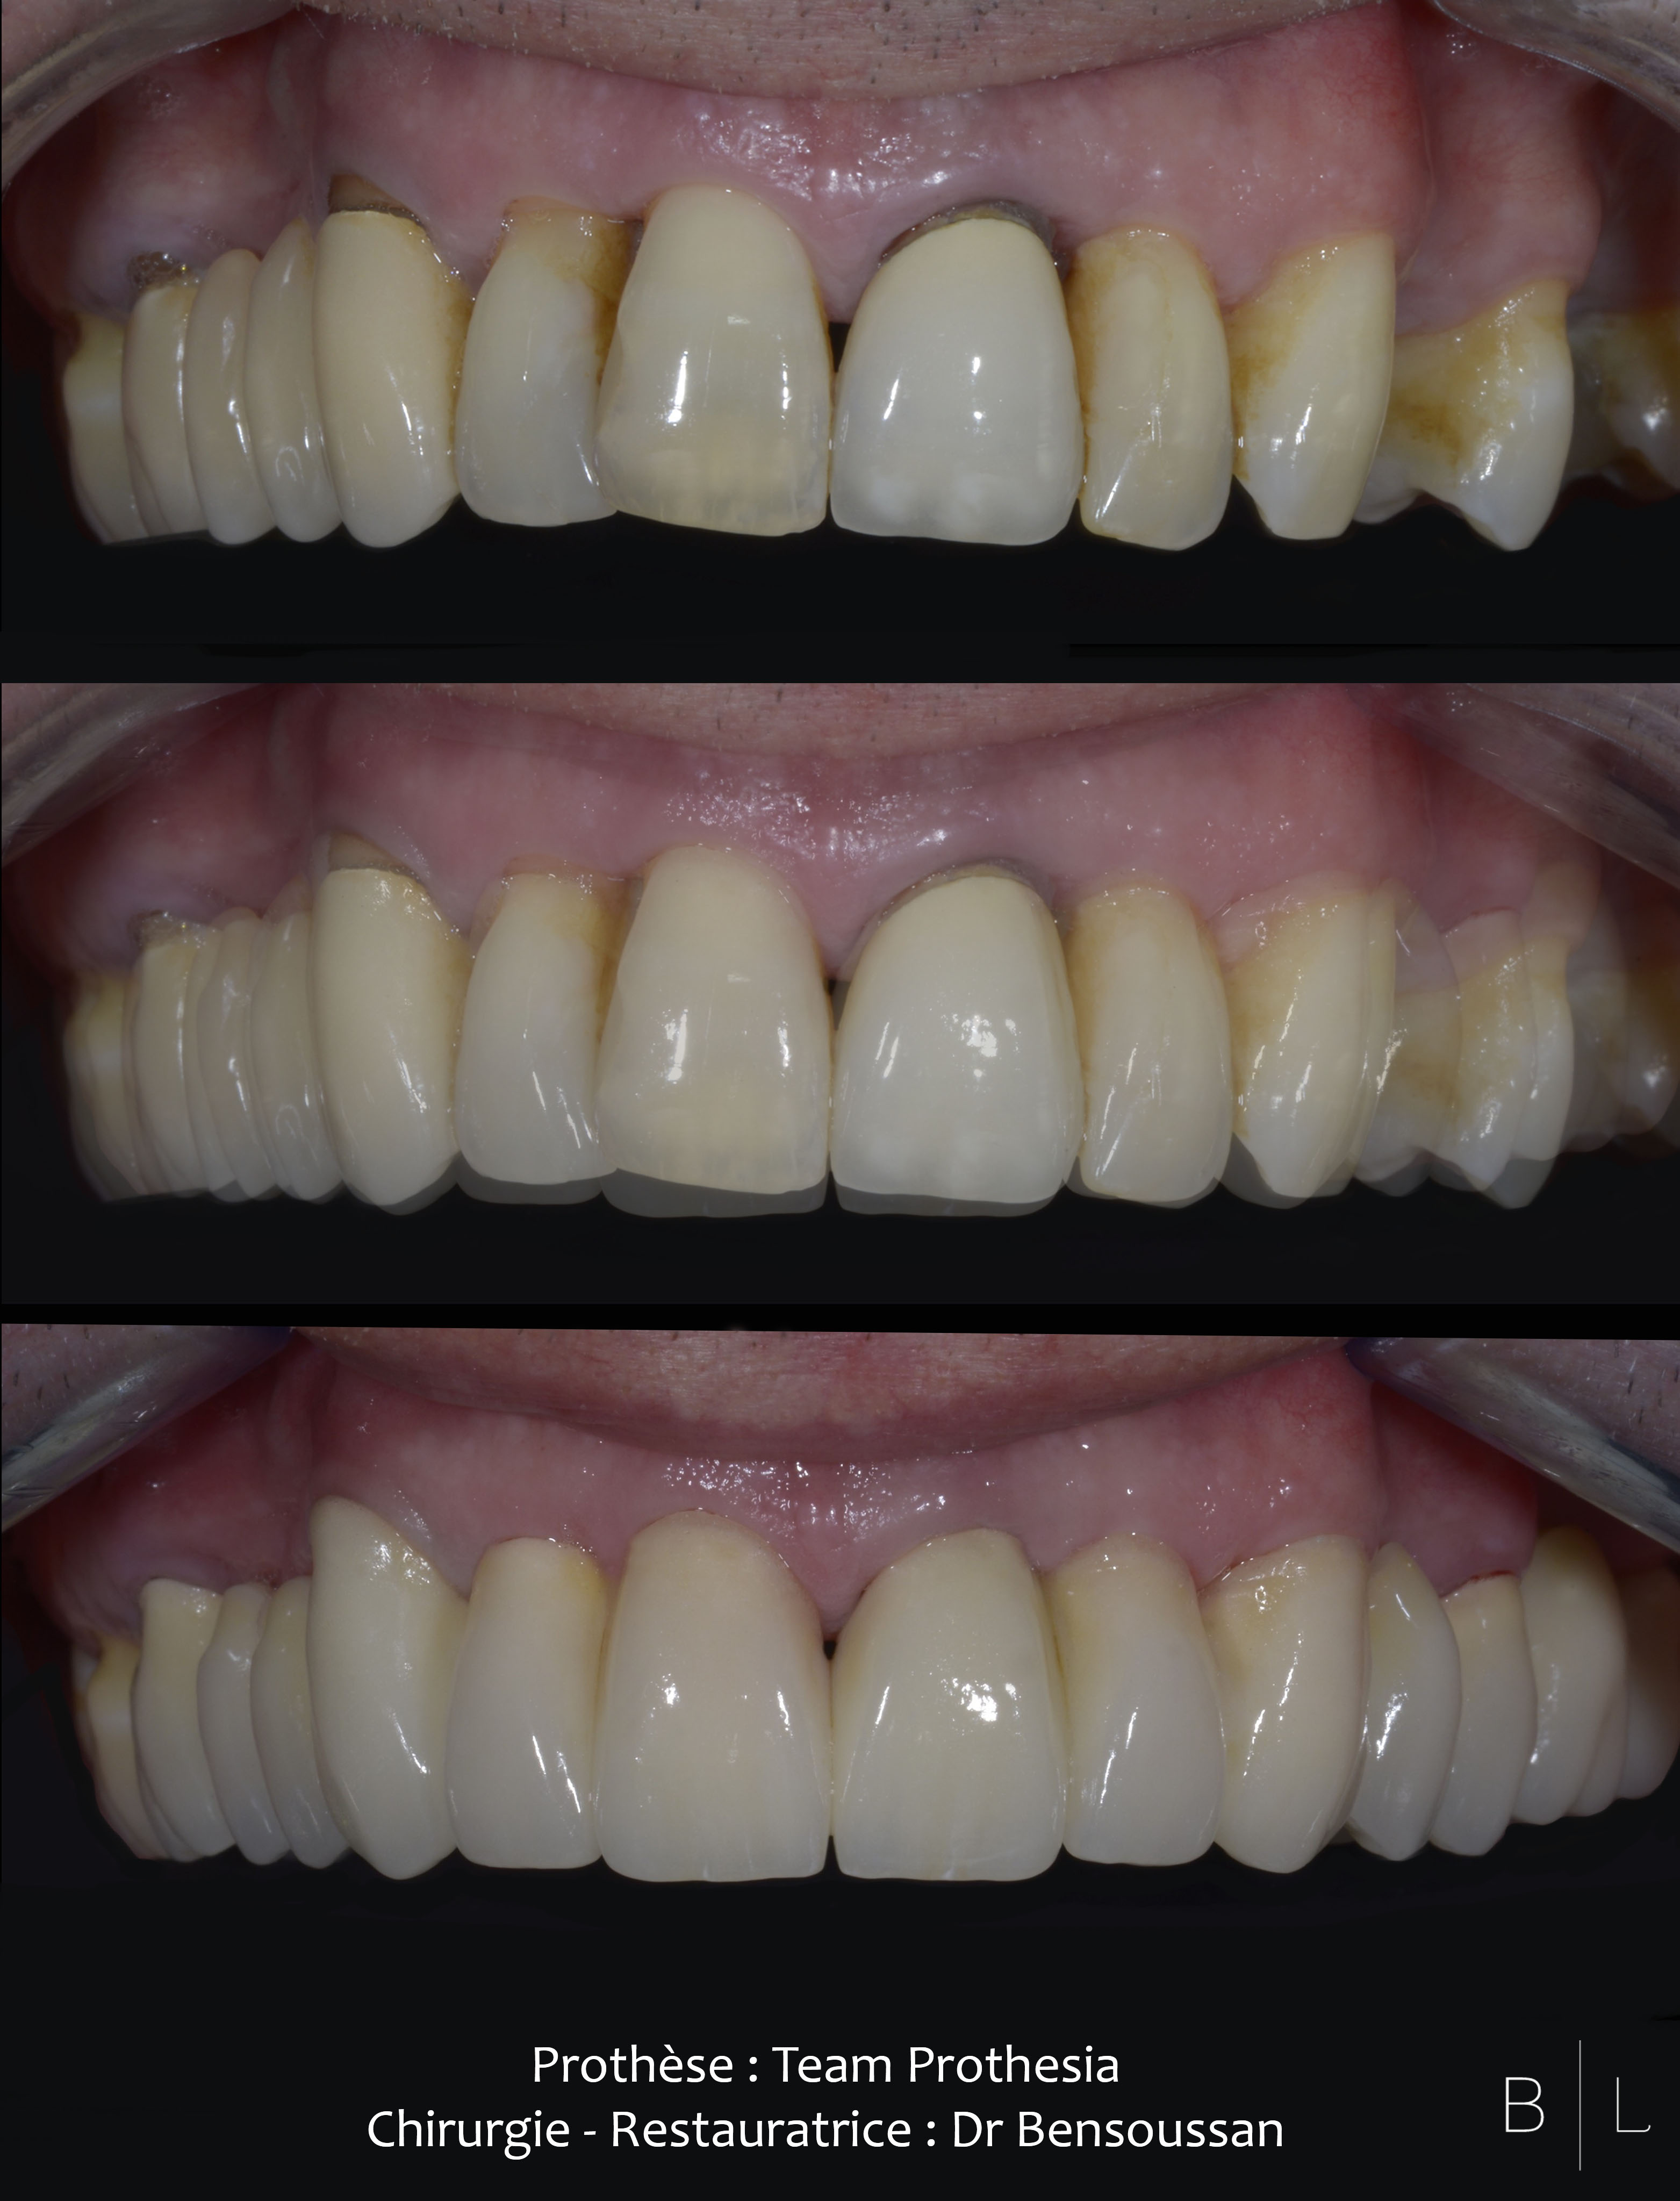

Emax by Team Prothesia - Surgery and Restorative by Dr Bensoussan.

Emax by Team Prothesia - Surgery and Restorative by Dr Bensoussan #ditramax #veneers #DSD #newsmile #BL